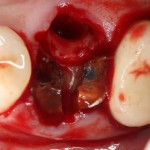

В лунку помещаем Neocones, Bioss Collagen:

Затем к краям лунки подшивается Mucograft Seal:

После чего можно заняться лункой зуба #45. Там тоже гранулема. Немаленькая:

Которую мы удаляем, а саму лунку консервируем точно по такому же принципу, что и лунку #47 (Neocones, Bioss Collagen):

И «запечатываем» с помощью Mucograft Seal: